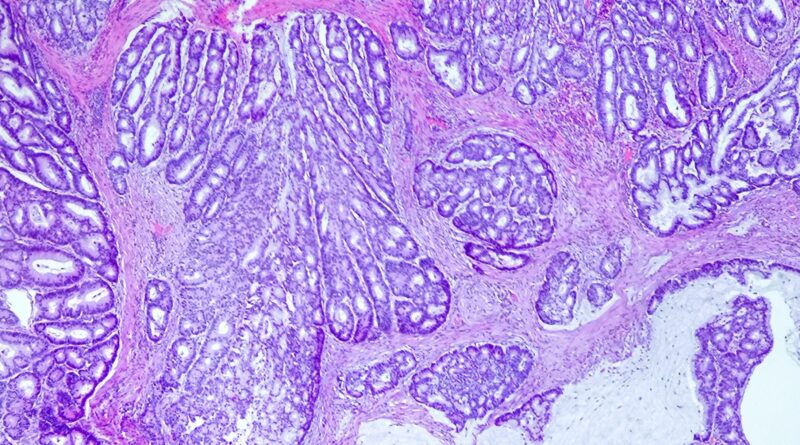

Obrazy mikroskopowe:

- przekraczający mięśniówkę śluzówki naciek składający się z komórek wykazujących cechy atypii dużego stopnia (powiększone, pęcherzykowe, ciemne jądra komórkowe, zaznaczone jąderka, liczne figury podziału) tworzących układy sitowate (krzyżyk) i cewkowe

- ponadto w obrębie guza obecne są pola śluzu (gwiazdka) z zatopionymi w nich grupami, zespołami i pasmami atypowych komórek walcowatych (czerwona strzałka) oraz z komórkami sygnetowatymi – jądra komórkowe ciemne, zepchnięte na obwód przez położoną centralnie jasną wodniczkę (niebieska strzałka)

- pola śluzowe z komórkami walcowatymi lub sygnetowatymi stanowią mniej niż 50% objętości guza, komórki sygnetowate są zanurzone w polach śluzu, brak cech innych podtypów raka jelita grubego

Rak gruczołowy jelita grubego z komponentą śluzotwórczą (Adenocarcinoma of the colon with mucinous component).